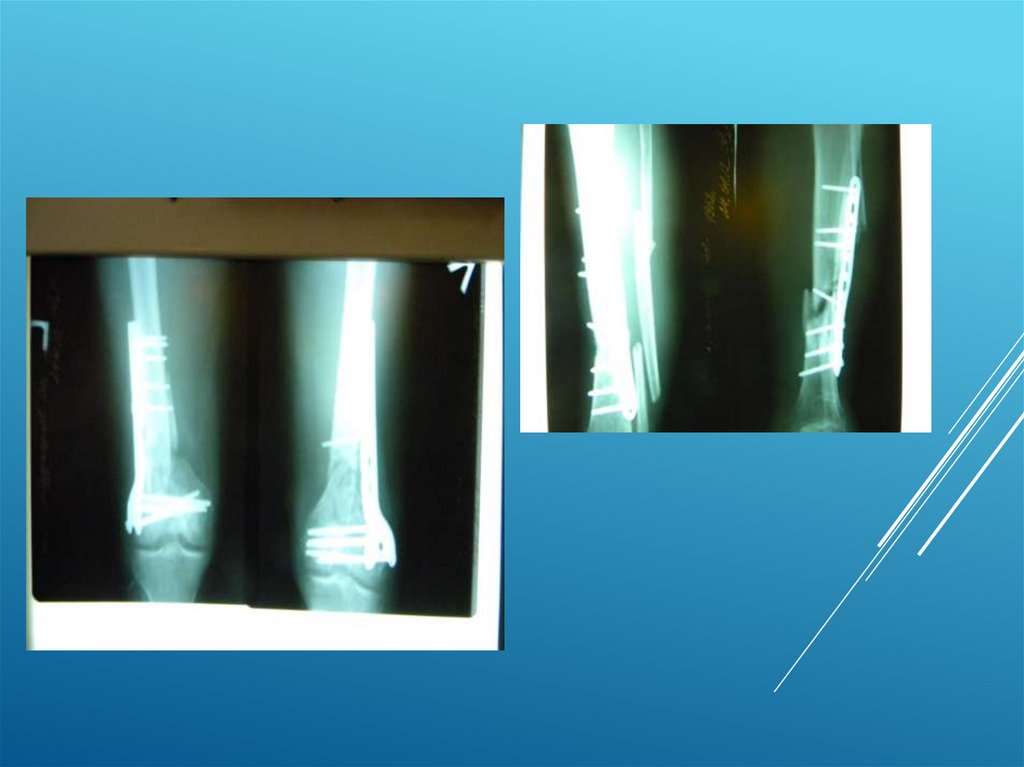

Пациент С. 28 лет

21.

22.

23.

24.

25.